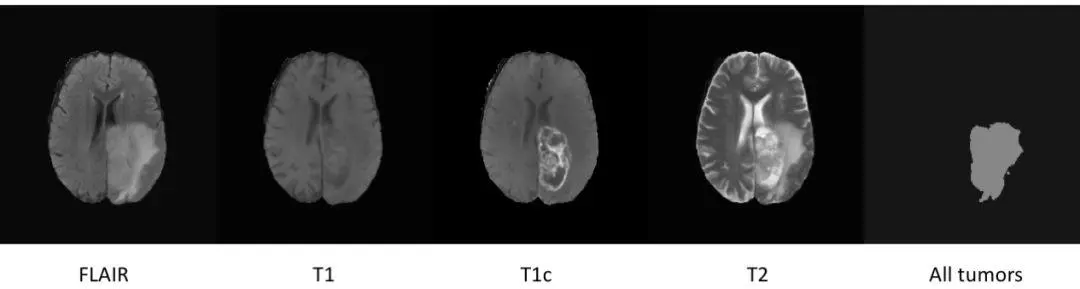

有了上述分析,下面给出一个具体的分割实例。这个例子不仅可以区分出脑部区域,而且能够用于脑部肿瘤的识别和分割。下图是肿瘤分割过程示意图。

这个例子用到了 BRATS 2017数据集 ,数据扩张处理如下图所示: